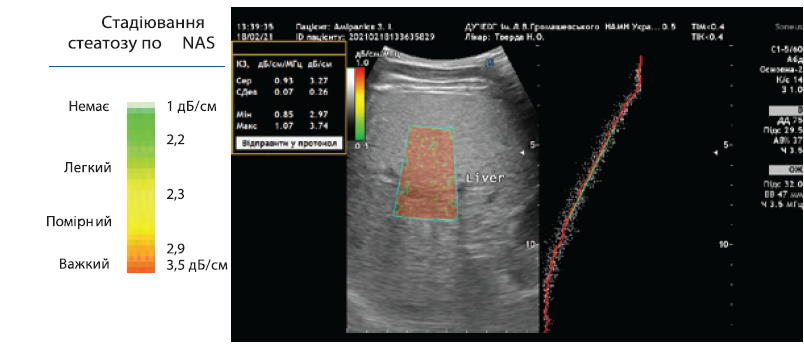

УЗ-дослідження печінки у В-режимі (В-УЗД)і стеатометрія – кількісне визначення ступеня стеатозу за допомогою виміру коефіцієнта затухання (ВКЗ, дБ/см).

Для визначення вираженості стеатозу використовується шкала (дБ/см), яка корелює зі ступенем стеатозу за даними біопсії печінки.

NAS (NAFLD activity score — шкала активності неалкогольної жирової хвороби печінки):

S0 — немає стеатозу: < 2, 19 дБ/см;

S1 — мінімальний стеатоз: < 5% гепатоцитів зі стеатозом; 2,2–2,29 дБ/см;

S2 — помірний стеатоз: < 6–32% гепатоцитів зі стеатозом; 2,3–2,9 дБ/см;

S3 — виражений стеатоз: < 33–100% гепатоцитів зі стеатозом;

> 2,9 дБ/см.